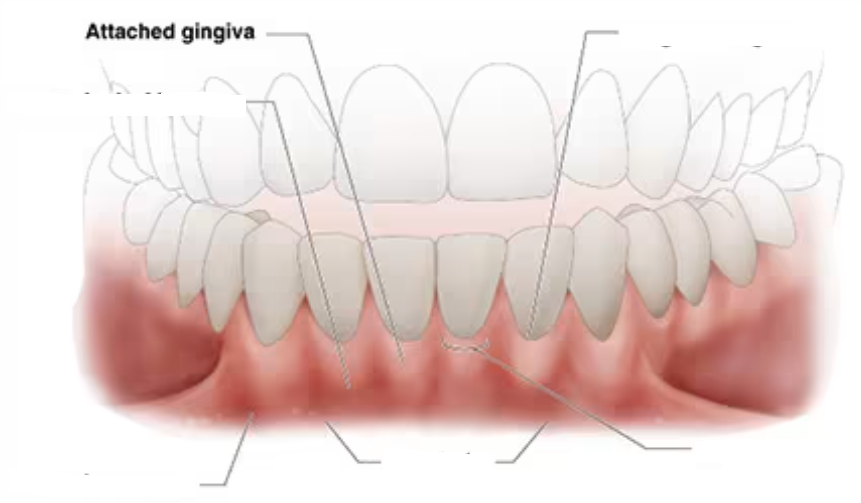

mucogingival junction

clinically visible boundary where the pink attached gingiva meets the red, shiny alveolar mucosa

clinically visible (demarcations)

attached gingiva (where is it thinnest?)

continuous with the free gingiva is tightly bound to cementum on the cervical-third of the root and periosteum of the alveolar bone

lies between the free gingiva and the alveolar mucosa

thinnest in the premolar region